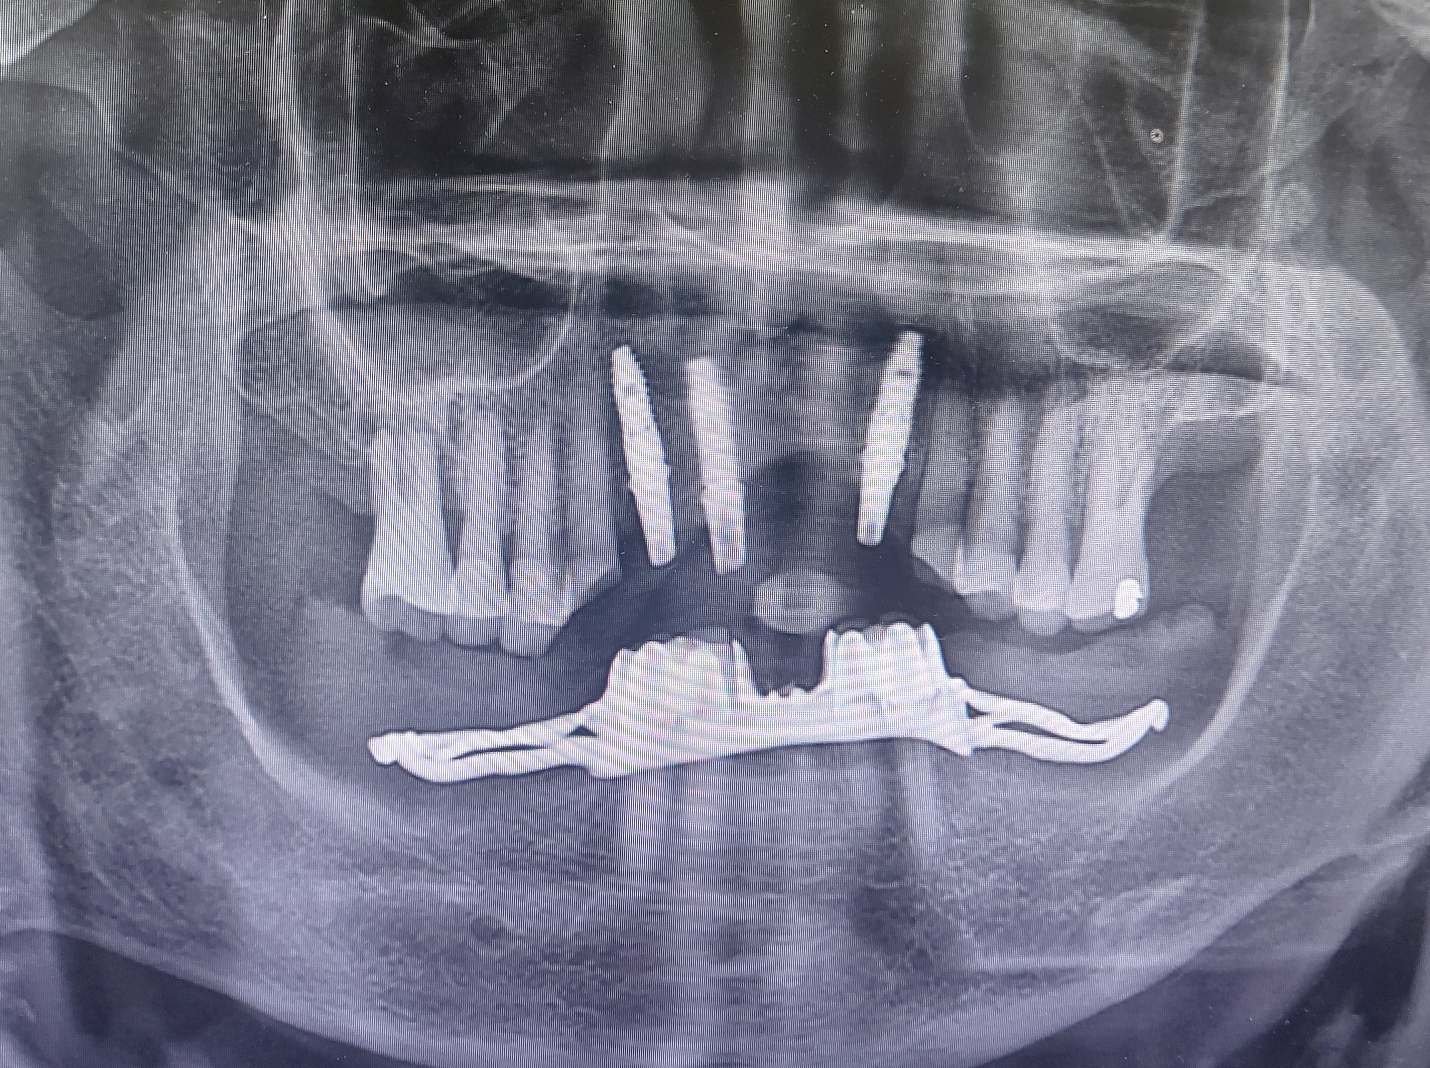

수술시 충분한 골 두께가 나와서 직 후 지대주를 연결하고 바로 인상을 채득하였습니다.

저희 병원의 프로토콜에 따라 5일뒤 실밥을 제거하고 임시 치아를 바로 올려 드렸습니다. 치료 결과에 만족 하셨습니다.